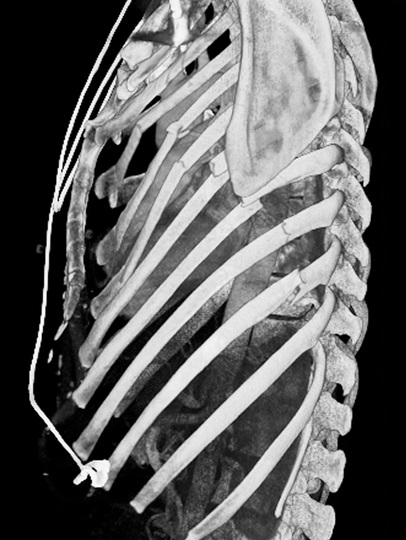

Même cas en

recontructional sur 3D . La fracture affecte sur

tout les côtes gauche ( 3th -9th ) de flanc gauche

du thorax |